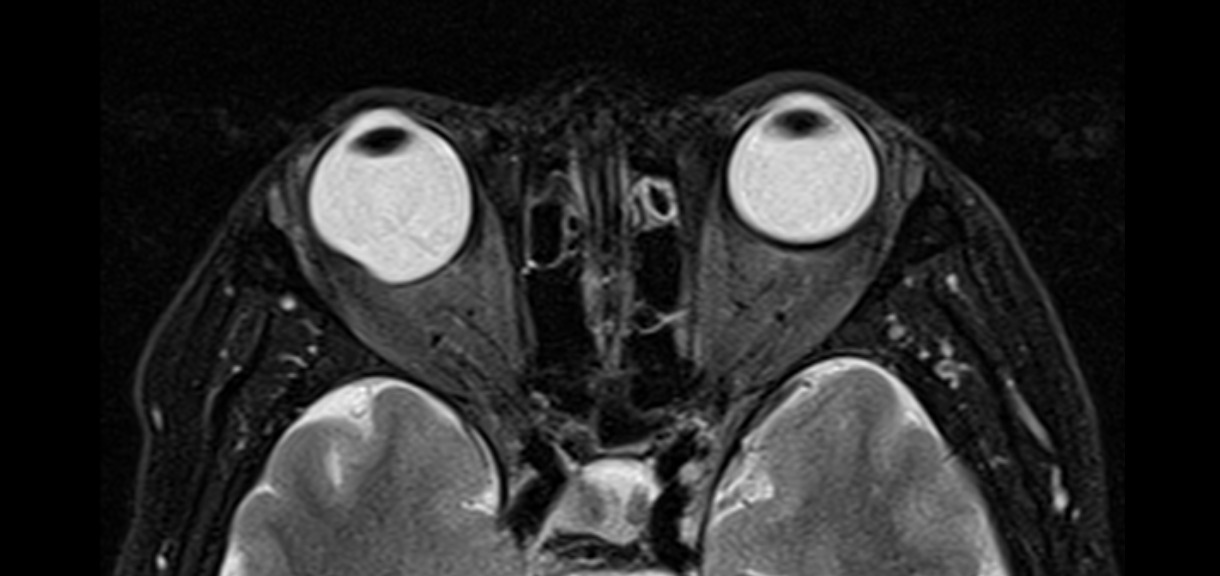

Resonancia Magnética de Órbita

Cortes axiales de resonancia magnética de órbitas en el cual se aprecia aumento del tamaño del globo ocular derecho a expensas de su eje anteroposterior, acompañado de adelgazamiento de su pared posterior lo cual corresponde a estafiloma. Estafiloma Definición:...